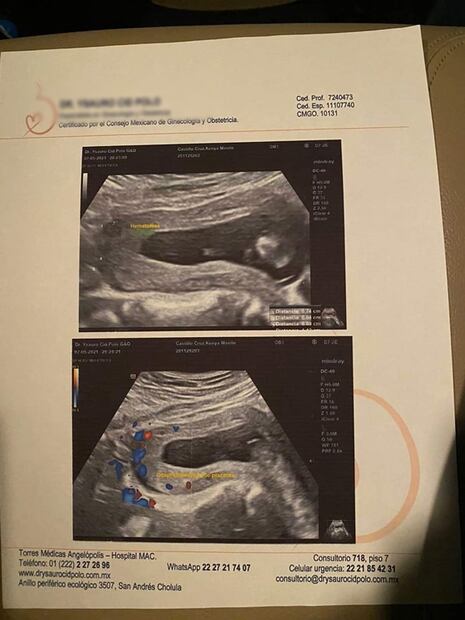

El hombre la dejó con amenaza de aborto , hematomas internos, desprendimiento de placenta , tabique desviado y esguince en el cuello.

Kenya también hizo públicas las fotografías que evidencian las heridas y los golpes que sufrió, también incluyó exámenes médicos que advierten una amenaza de aborto.